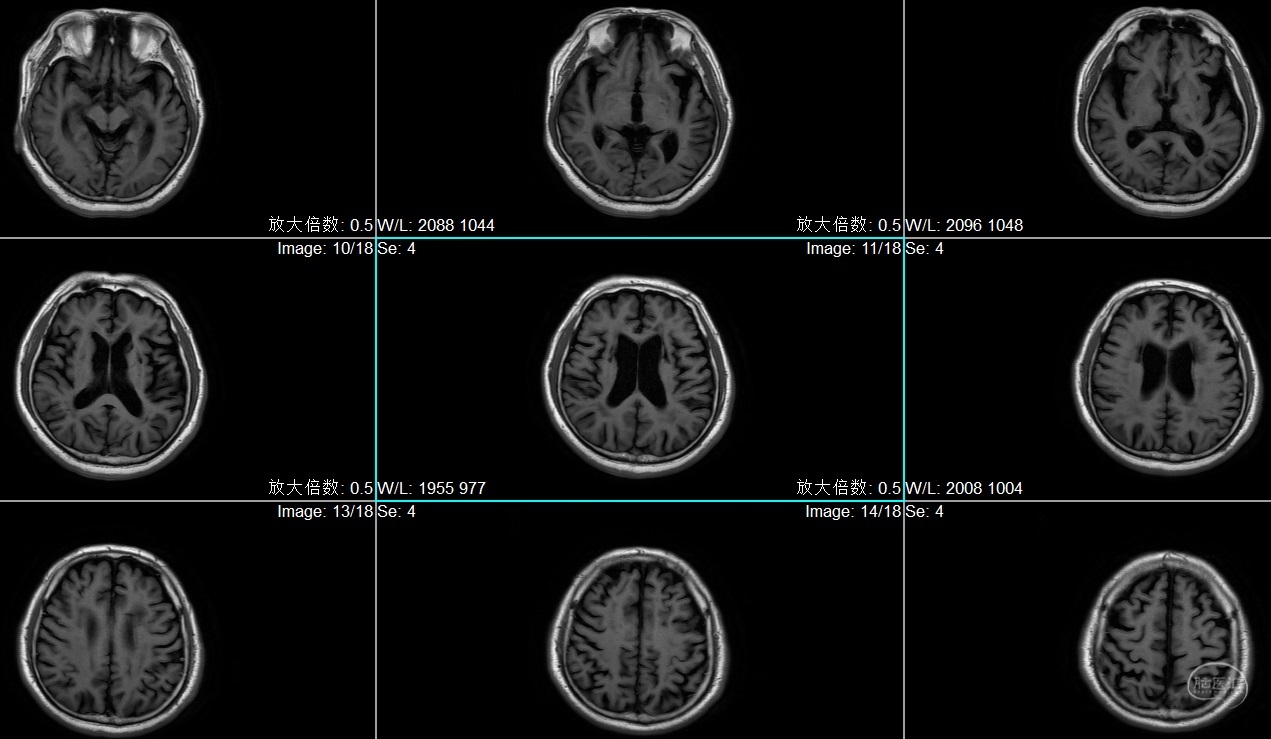

患者李XX,男性,63岁,主因右肢无力1月入院

既往高血压病史,糖尿病史,脑梗死病史5年,遗留优质活动不利,冠心病病史

查体:BP:129/75mmHg,神情,言语正确,四肢从嘱,GCS:15分,双侧瞳孔各3mm,对光反射灵敏,右侧肌力4级,左侧5级

患者李XX,男性,63岁,主因右肢无力1月入院

既往高血压病史,糖尿病史,脑梗死病史5年,遗留优质活动不利,冠心病病史

查体:BP:129/75mmHg,神情,言语正确,四肢从嘱,GCS:15分,双侧瞳孔各3mm,对光反射灵敏,右侧肌力4级,左侧5级